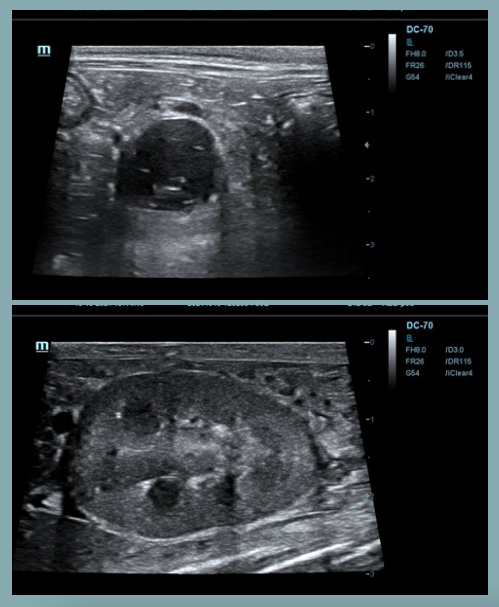

Sombra acústica

- Las ondas de sonido no pueden atravesar una estructura densa (material mineral) o un estrato de gas.

- La imagen generada presenta una línea superficial hiperecogénica que describe la superficie de la estructura, a partir de la cual, pierdo completamente la visualización de los estratos profundos (región oscura).

Artefactos: Refuerzo posterior

- Las ondas sonoras pasan a través de un tejido de baja densidad (fluido) y presentan una mayor intensidad respecto a otras ondas en el mismo plano de profundidad.

Artefactos: Sombra de borde

- Se forma en los bordes de estructuras curvas o redondeadas, como un quiste, un vaso sanguíneo o una lesión nodular.

- La imagen muestra una sombra longitudinal a cada lado del borde de la estructura redondeada, debido a la refracción de las ondas en el borde estructural.